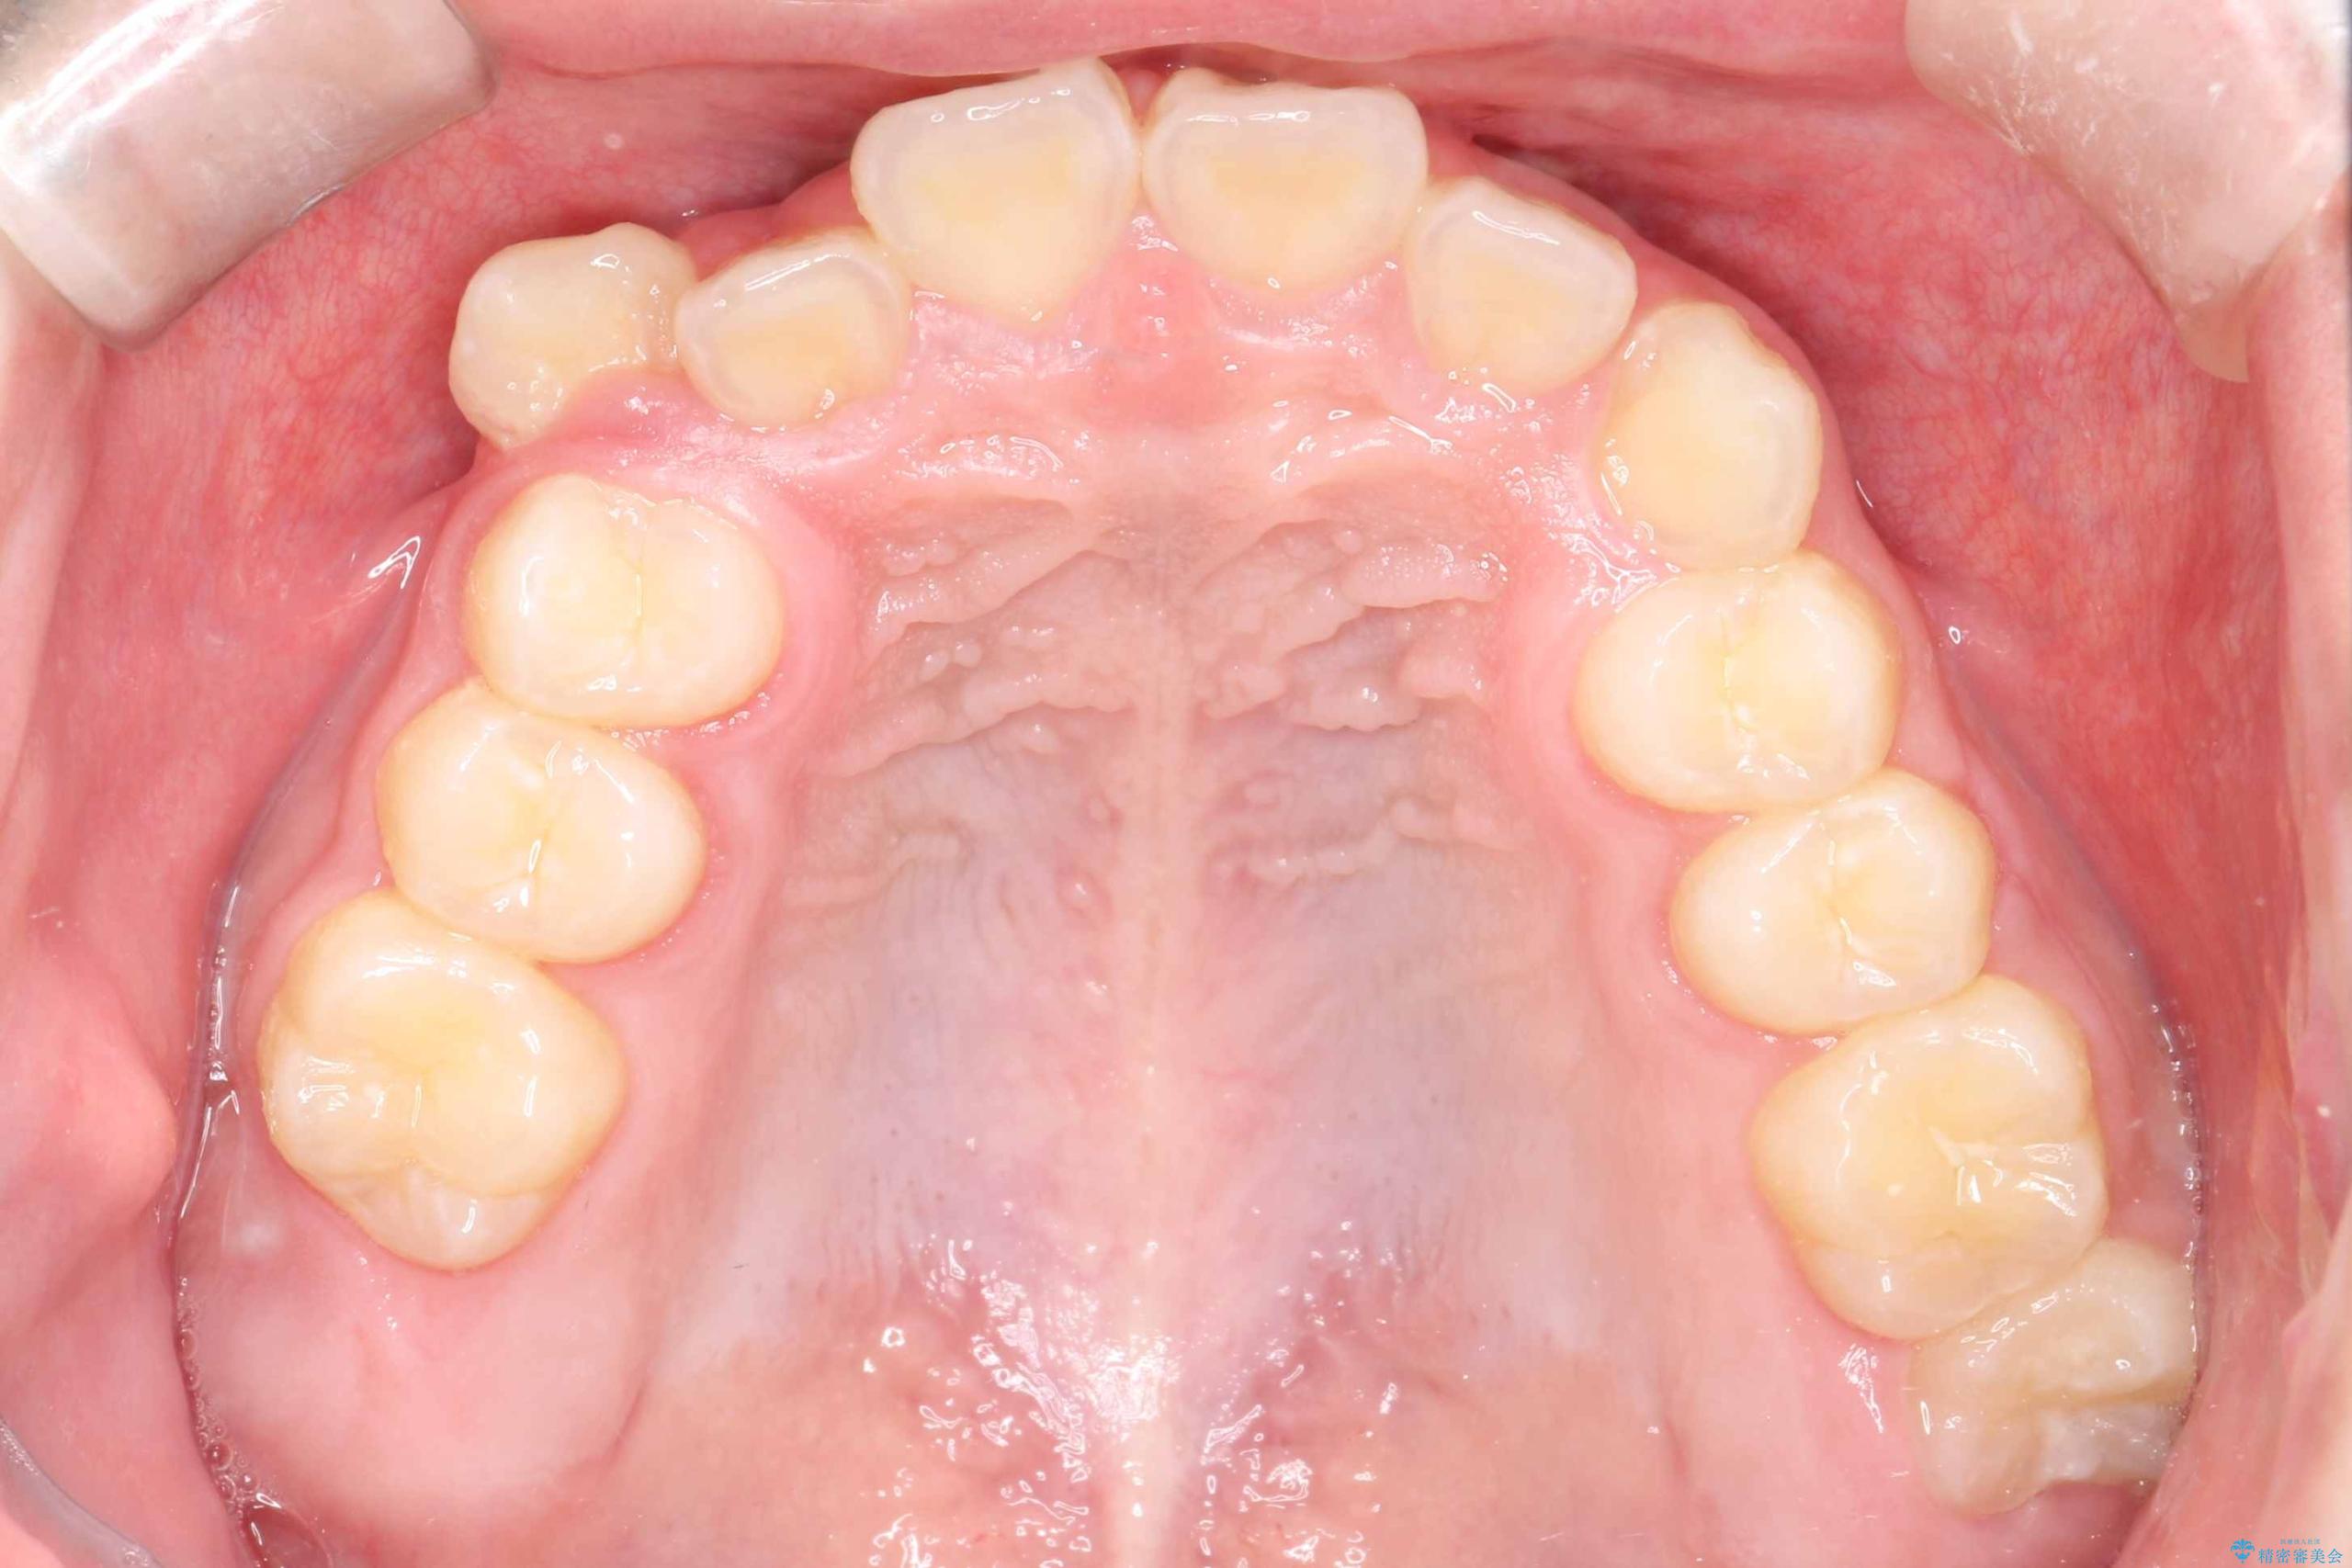

八重歯・歯並びのデコボコとディープバイトを改善した抜歯ワイヤー矯正症例

- 八重歯と咬み合わせを治したいを主訴にご来院された患者様です。

矯正の精密検査の結果上顎左右4番の計2本を抜歯し、審美性に配慮したワイヤー矯正装置(審美装置)を用いて治療を行いました。

八重歯などの歯列のデコボコが綺麗に改善され、患者様にも大変喜んでいただけました。また、咬み合わせが深い「ディープバイト」も併せて改善し、見た目だけでなく機能面でもバランスの取れた咬合を獲得しています。